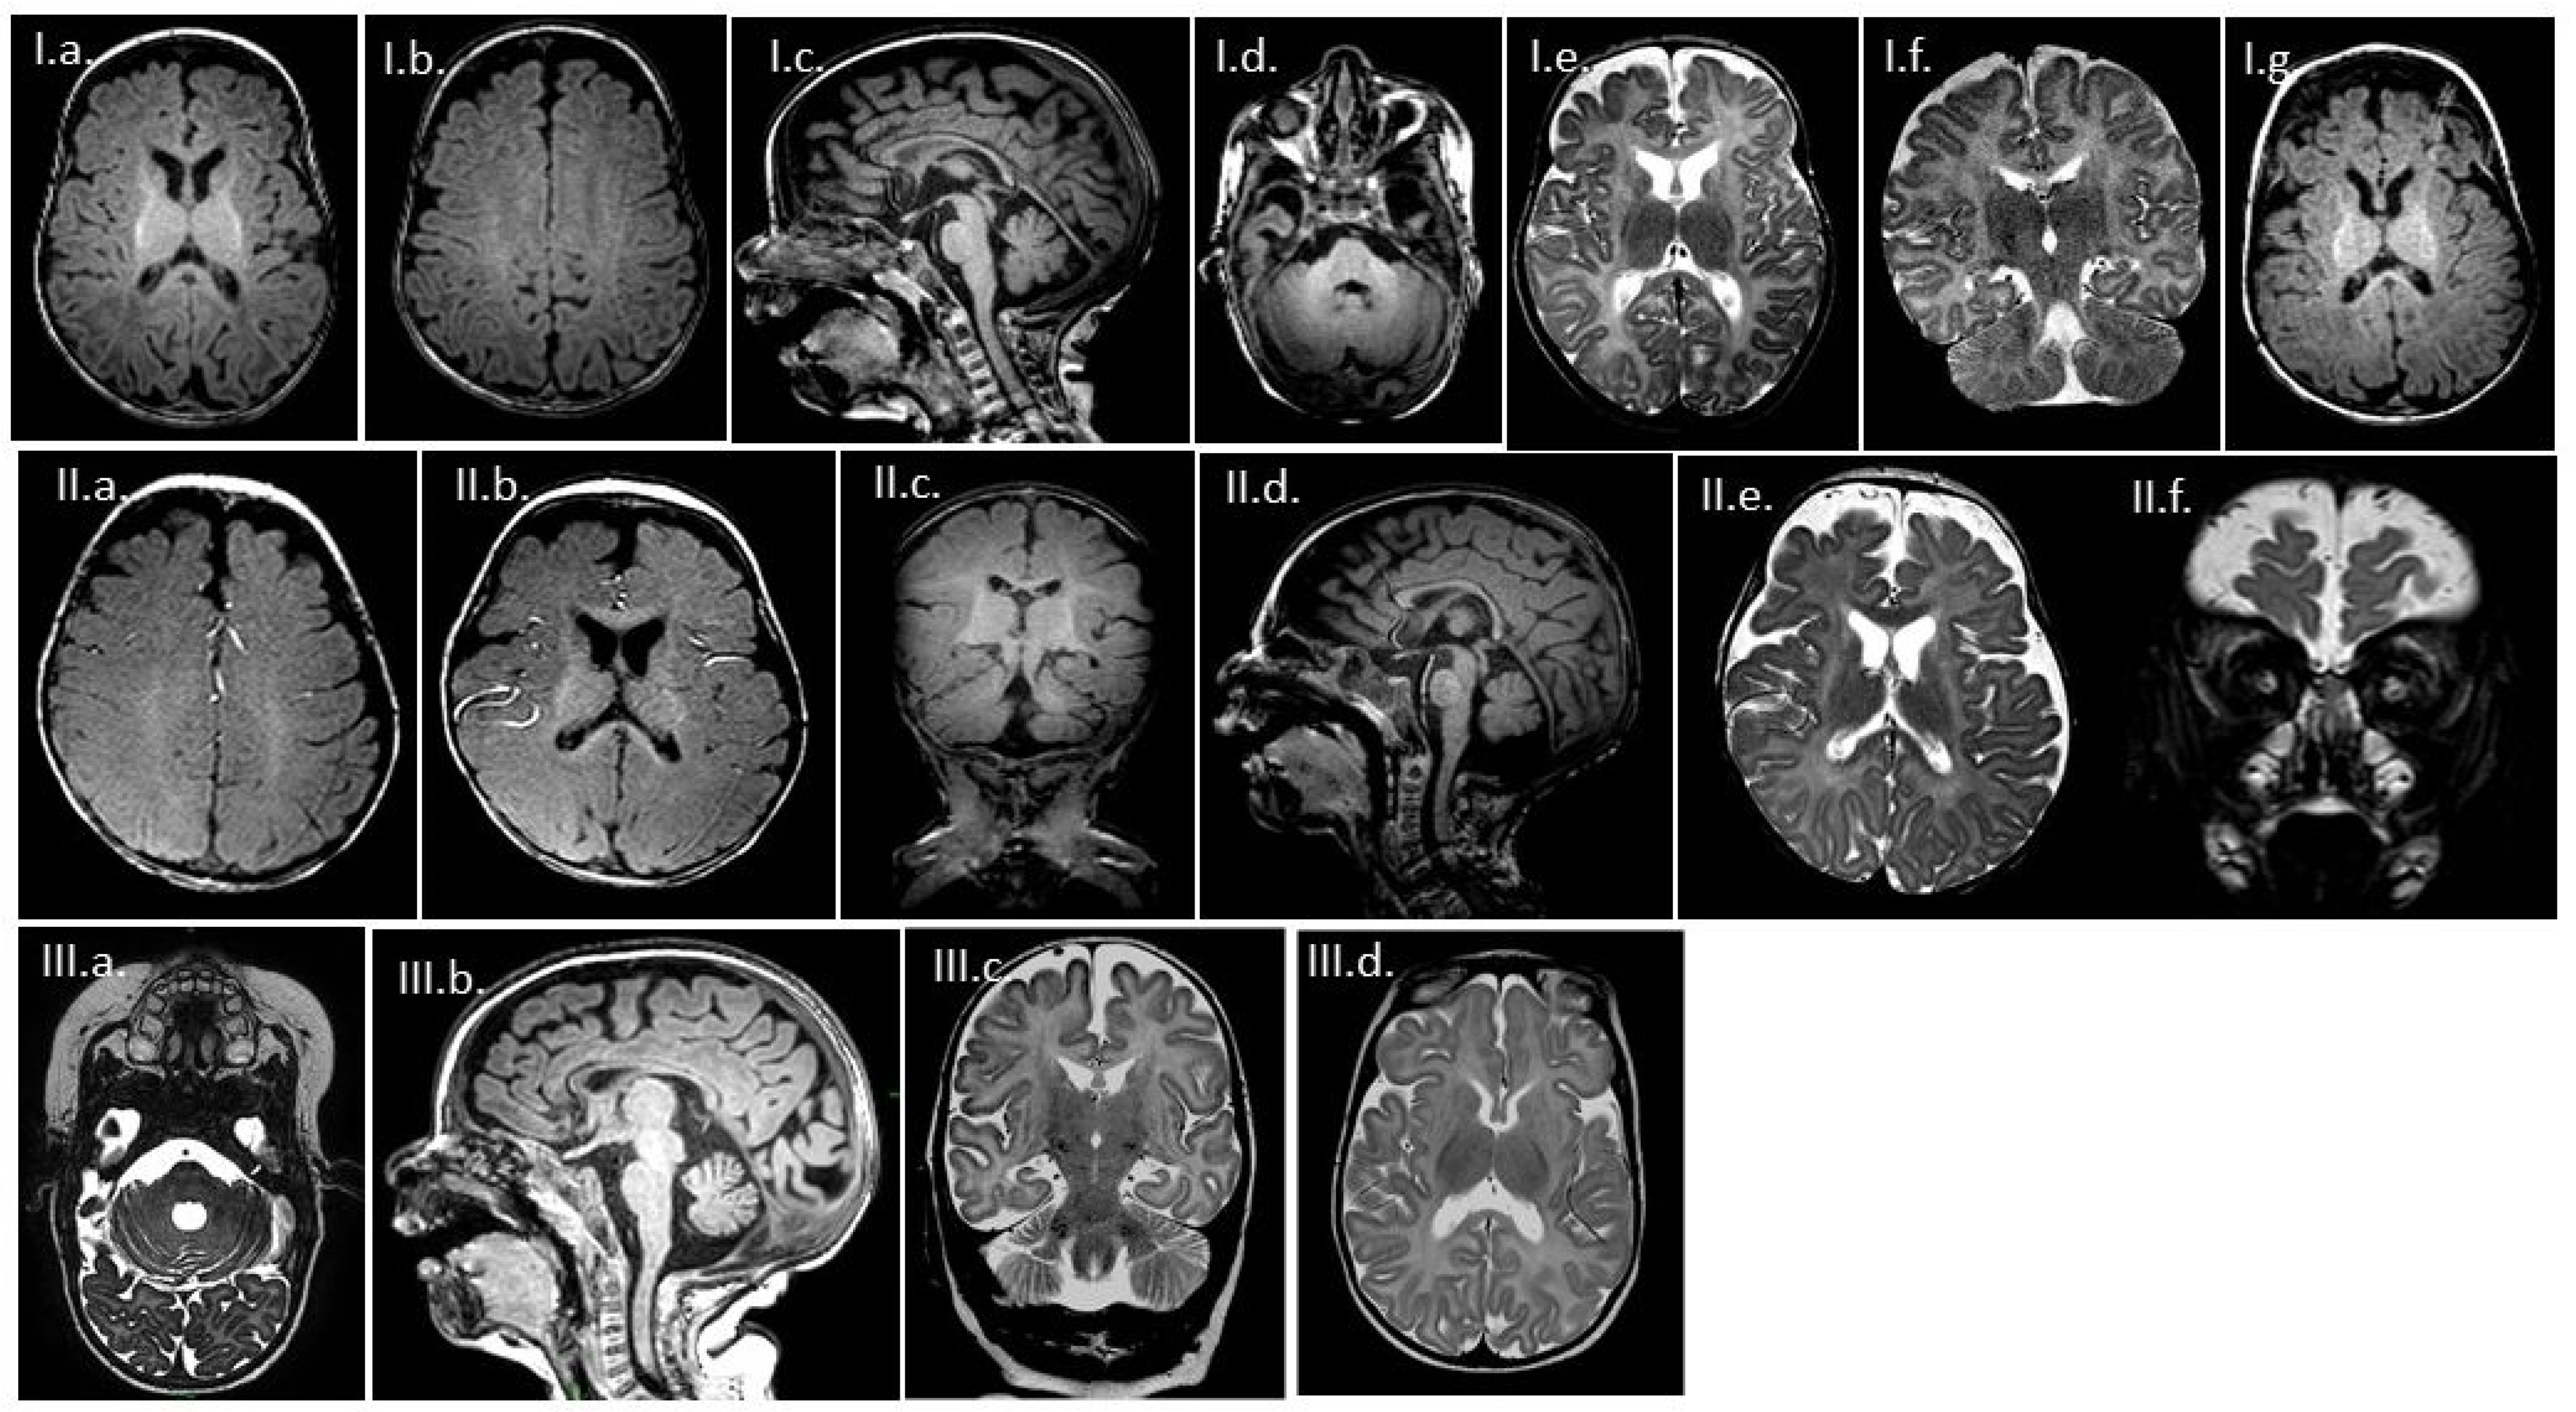

3.2. MR Findings